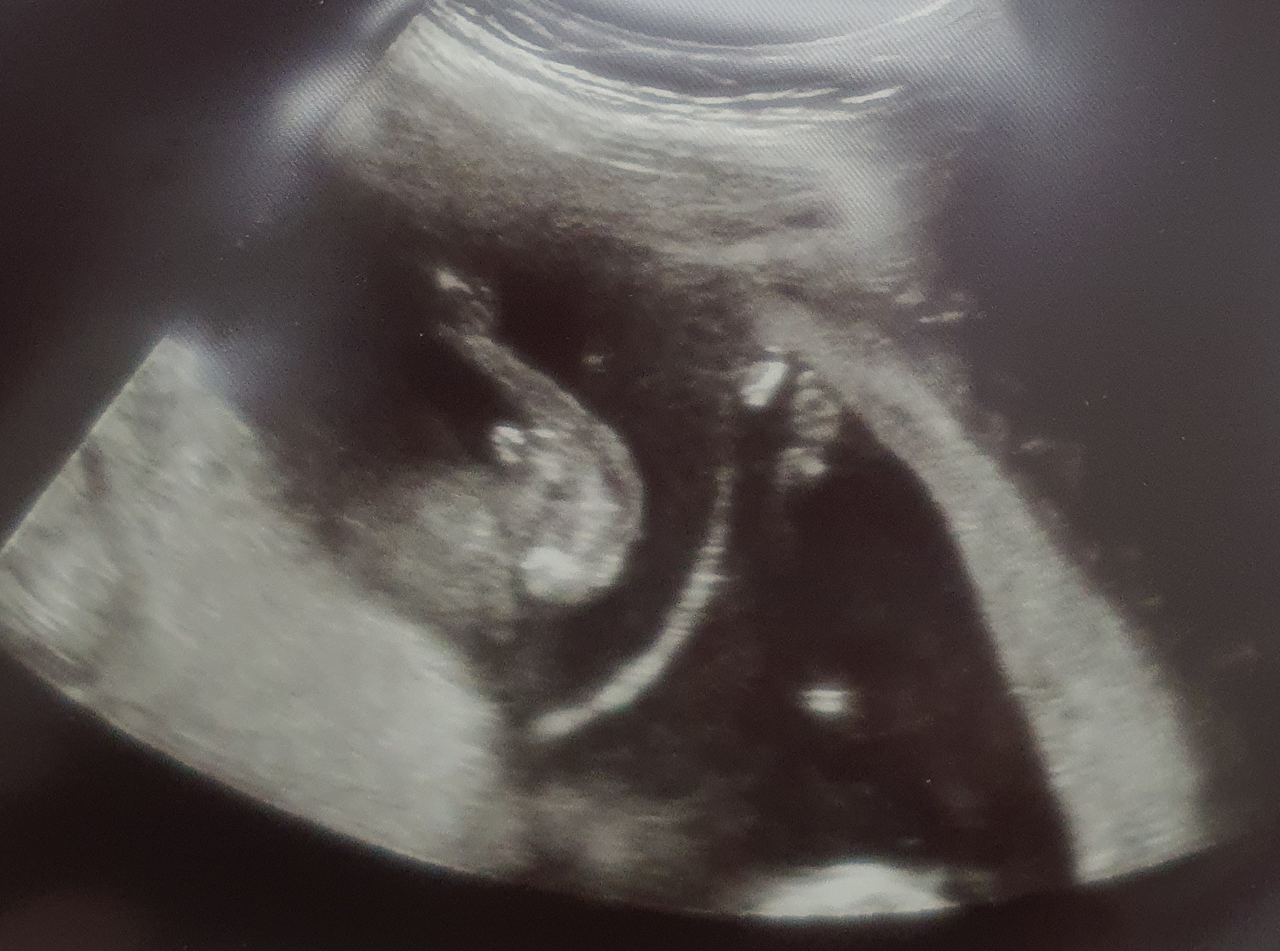

교수님을 만나기 전, 초음파를 먼저 보았다. 보통은 16주에 성별이 정확히 나오지만 빠르면 14주에도 성별을 알 수 있다. 세쌍둥이 임신을 알자마자 셋 다 딸이면 좋겠다는 생각을 했다. 아기옷을 구경해도 딸옷만 예쁘고, 커서도 딸이 더 예쁠 것 같고, 그냥 이유 필요 없이 무조건 딸을 키우고 싶었다. 그러다 문득, 그래도 애가 셋인데 아들이 하나도 없으면 그것도 섭섭하겠다 싶었다. 그래서 일란이 둘은 딸, 이란이 하나는 아들이라고 내 마음대로 정해놓고 지내던 참이다.

“아들 둘에 딸 하나네요.”

"일란성쌍둥이 중 하나가 탯줄이 중간에서 나오지 않고 구석에서 나오고 있어요. 이럴 경우 영양분이 제대로 공급되지 않아 성장 지연이 올 수 있고, 그렇게 되면 다른 일란성쌍둥이도 잘못될 수 있어요."

존재감 뿜뿜 아들(내가 바로 아들이다)